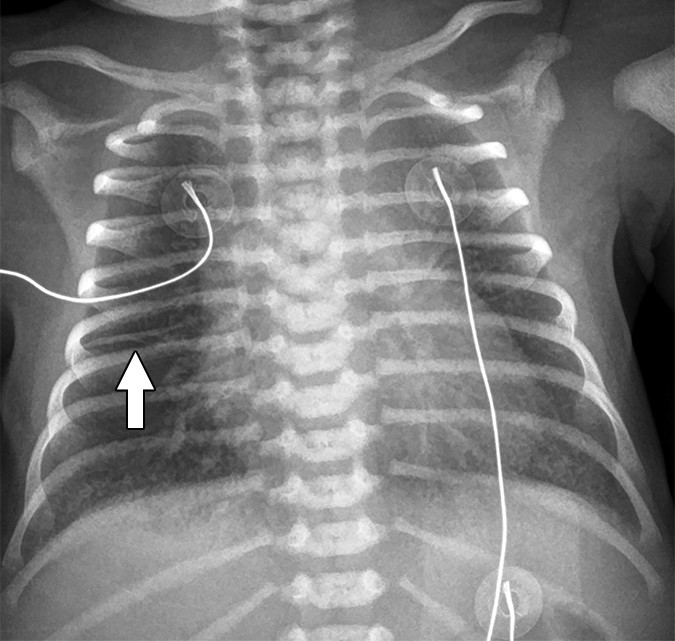

TTN (Transient Tachypnea of the Newborn) Perihilar streaking; fluid in fissures (especially right minor fissure); symmetric; resolves within 24–48h Term or near-term; delayed clearance of fetal lung fluid; benign and self-limited